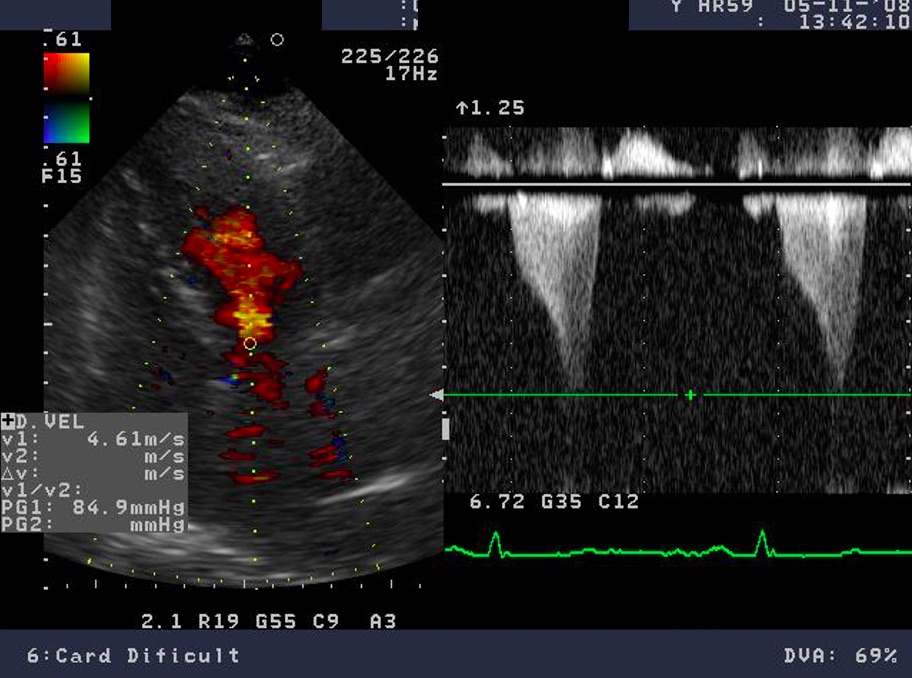

The most specific feature of the myocardium in HCM is the reduced contractile stress (the force per unit area) because of the cardiomyocyte disarray and interstitial fibrosis [33, 37]. A maintained ejection fraction is explained by the increased end-diastolic wall thickness that produces an augmented thickening, but the histopathology of this disease is characterized by myocardial hypertrophy, fiber disarray, increased loose connective tissue, and fibrosis, which are all thought to interfere with force generation and relaxation of the cardiac muscle. Both speckle tracking and tissue Doppler highlight this feature, with a significantly lower longitudinal systolic strain, systolic strain rate, and early diastolic strain rate (see Fig. 7) [27, 28, 30, 37]. GLS is independently associated with outcomes in HCM patients. A GLS with a value higher than –10 percent is associated with a higher risk of adverse events. This depressed contractility function of the LV correlates also with myocardial fibrosis and predicts ventricular arrhythmias. Through strain echocardiography an important prognostic parameter can be obtained: the mechanical dispersion, defined as the standard deviation of time from the onset of the QRS to peak negative strain. This is related to the amount of fibrosis and is also an independent predictor for arrhythmias [28].

Fig. 7.Echocardiographic aspect of HCM. (A) Apical 4 chamber view shows left ventricular hypertrophy. (B) The longitudinal strain bull’s eye plot derived from 2-D speckle tracking imaging shows a significantly reduced GLS (global longitudinal strain) of –8.1%, the most abnormal region is the basal septum, corresponding with the greatest wall thickness.